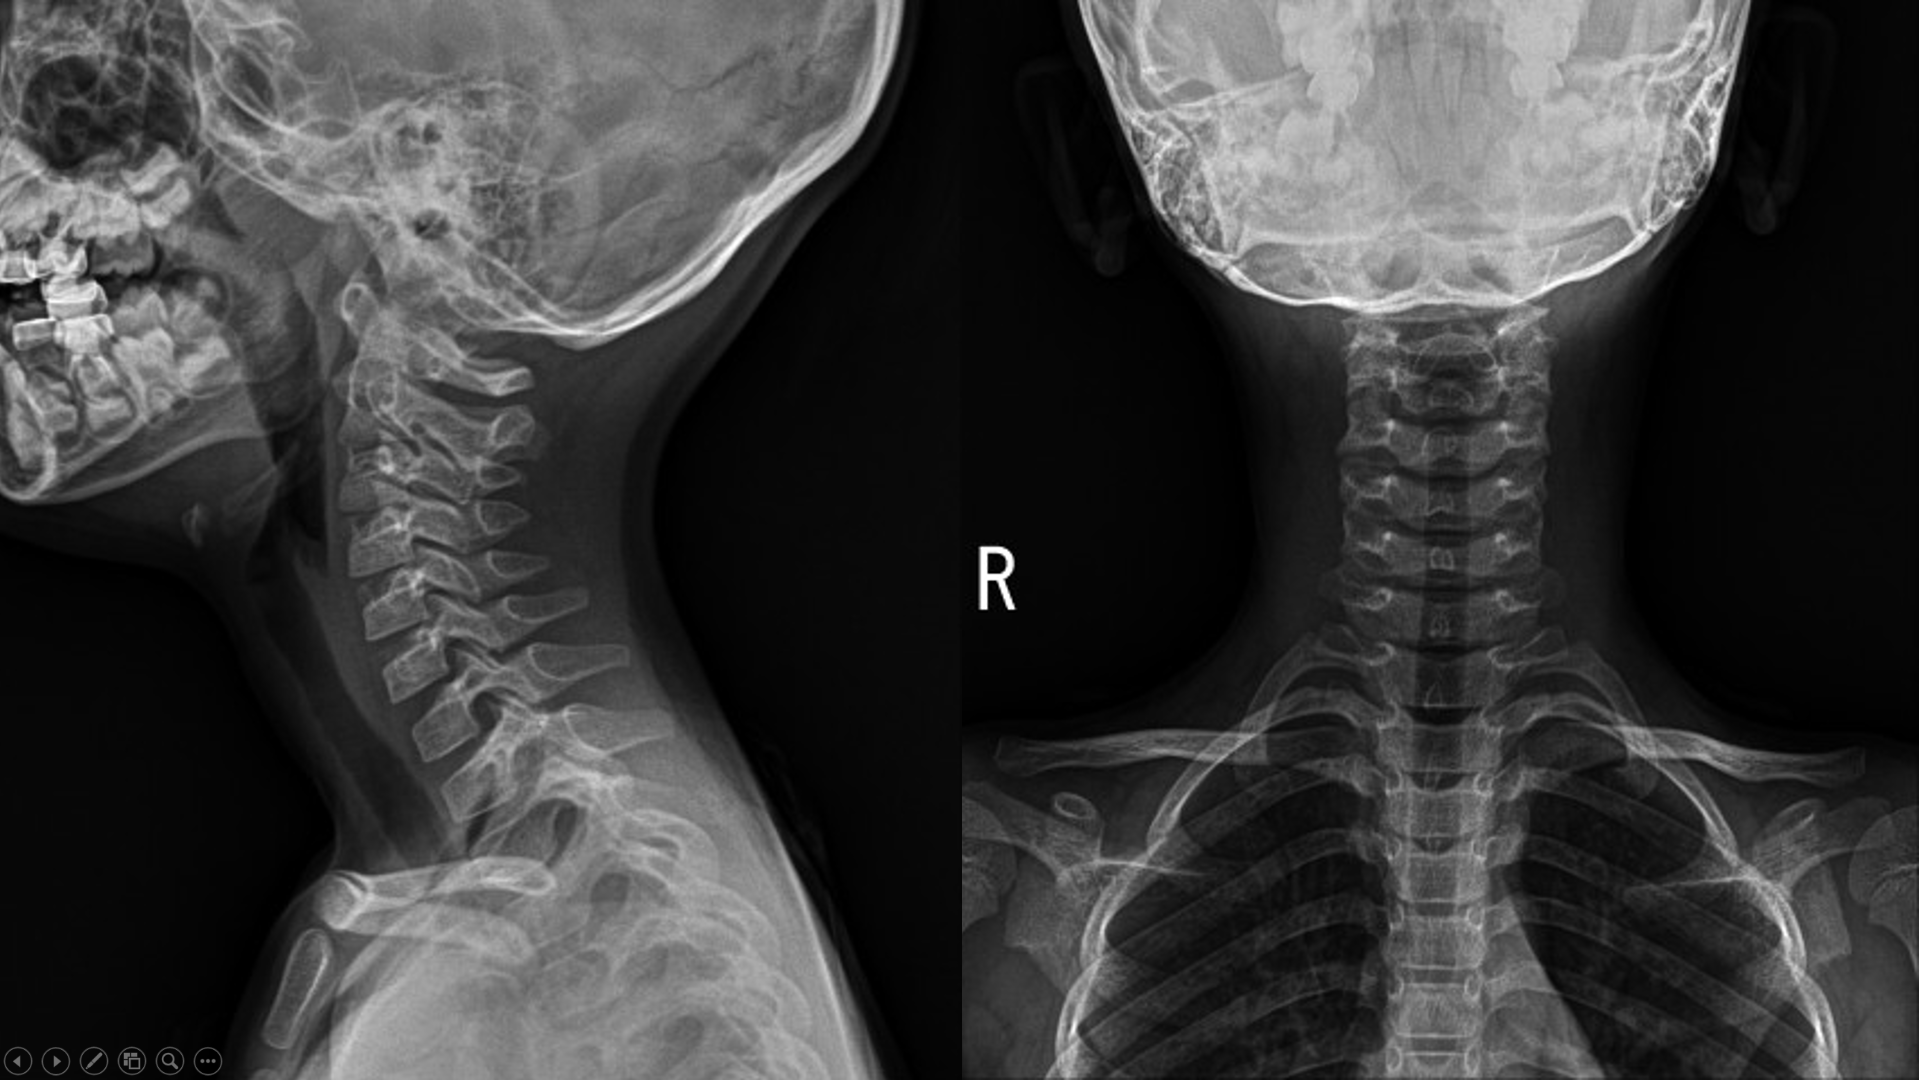

8년 전 6살 때 와서 촬영한 x ray..

비교해서 설명을 해주었는데..

"일단 목이 아파서 일자목으로 촬영될 가능성이 있지만, 일자목으로 보입니다."